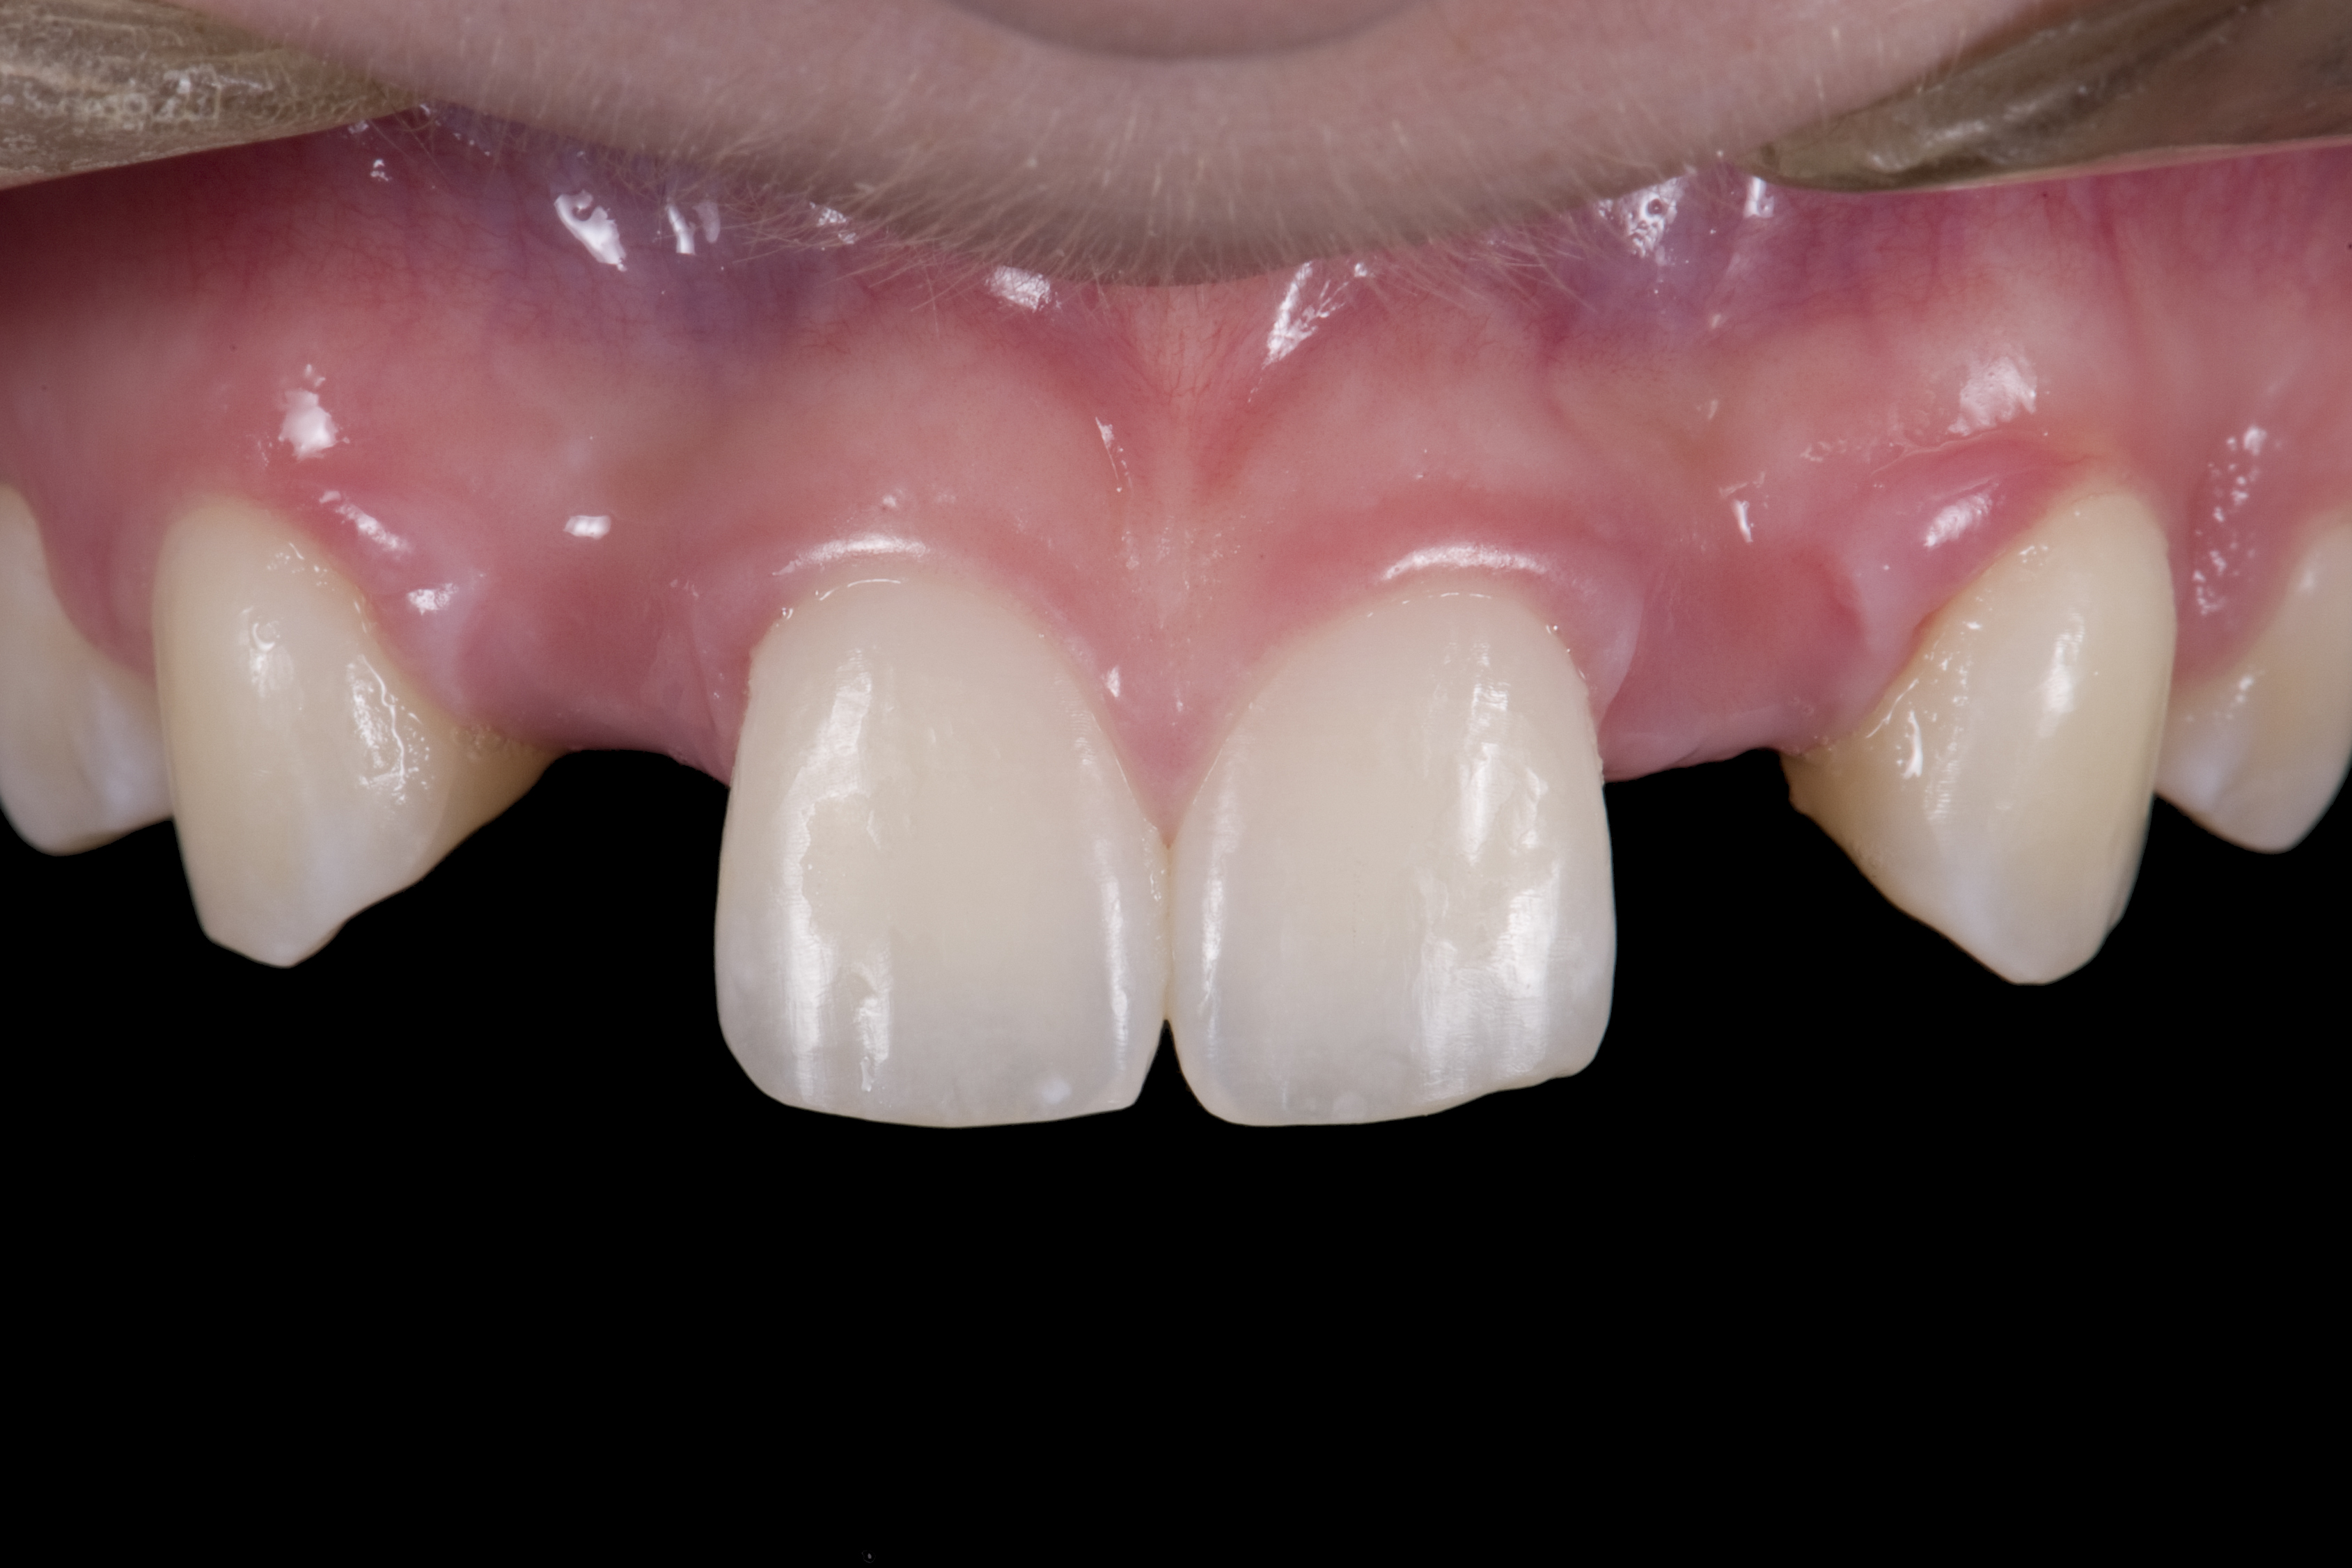

(1.) Initial presentation. Note midline shift to right, missing right lateral incisor, and diminutive left lateral incisor in crossbite.

Figure 1

A 14-year-old patient presented to the office with his mother (Figure 1). His chief complaint involved the large spaces between the teeth created by his missing right maxillary lateral incisor and his small left maxillary lateral incisor. He desired to replace the missing tooth with an implant and create a beautiful smile. Upon examination, he was found to have a class I canine and molar relationship, but because he had a tooth size/arch size discrepancy and space distal to the right central incisor, the remaining incisors had drifted to the right. The left maxillary lateral incisor was peg-shaped and in a cross bite position. Studies have shown a clear association between congenitally missing teeth and reduced tooth size.59-62 Because he was only 14 years old at the time and could not have implants placed until the cessation of growth (somewhere in the vicinity of 22 years old), he was sent to the orthodontist for alignment of the teeth.16,17 After 2 years of orthodontics, the appliances were removed, and his tooth coloration was improved using carbamide peroxide bleaching (Figure 2). Because some form of provisional needed to be placed until he was finished growing, a double-wing metal resin-bonded bridge was chosen. As discussed earlier, this is the ideal transitional prosthesis for patients that have congenitally missing maxillary lateral incisors. The benefits of this type of prosthesis include its ability to be removed and rebonded during the surgical phase of treatment and its ability to retain the roots in their proper position after orthodontic treatment.16 The final plan for the patient was to increase the width of the central and the maxillary left lateral incisor, utilizing porcelain laminate veneers to achieve the appropriate width/length ratio of 80%. A wax-up was created to idealize tooth size, a putty matrix was made from the wax-up to facilitate bonding of the incisors, and a non-precious, double-wing metal resin-bonded bridge was fabricated for lateral incisor replacement. Once the teeth were bonded to ideal size, the “Maryland Bridge” was fabricated from a polyvinyl arch impression with the newly bonded teeth (Figure 3). The metal frame was cast from a non-precious alloy to allow for fabrication of a very thin frame and to create a better surface for bonding. After sandblasting the internal aspect of the frame with CoJet™ silica (3M ESPE), accomplishing salinization, and executing cementation with a dual-cure resin cement, a fairly good adhesion to the frame was anticipated.29 The enamel surface was etched with phosphoric acid for 30 seconds, the primer (Single Bond Plus, 3M ESPE) was applied to both the internal surface of the sandblasted framework and the etched enamel, and the bridge was cemented with RelyX™ ARC (3M Espe) dual-cured resin cement (Figure 4 and Figure 5).